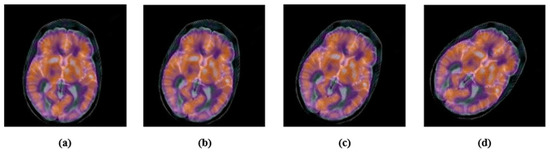

2.3. Accurate Computation of New Multi-Channel Gaussian-Hermite Moments of Color Images